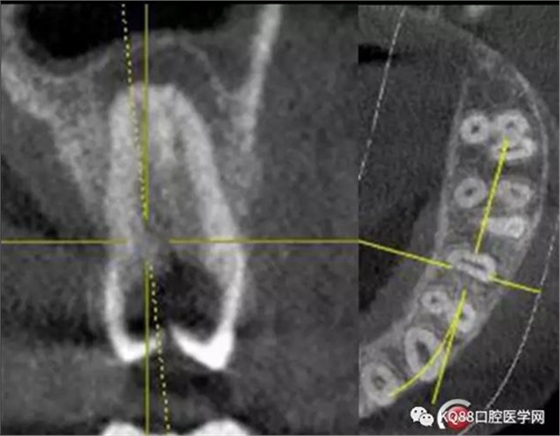

25遠(yuǎn)中鄰牙合面齲壞達(dá)髓腔,引起的牙髓炎,之后發(fā)展成為根尖炎的一個(gè)常見(jiàn)病例,上頜前磨牙,一看,心理都會(huì)覺(jué)得有啥啊,兩個(gè)根管,開髓后,直接擴(kuò)了,不會(huì)有任何壓力,幸運(yùn)的是我們有CT,所以我就開始都會(huì)定位下根管口,然后看到的事情告訴我其實(shí)上頜前磨牙不一定有我們想象的那么簡(jiǎn)單。

這兩張角度的截圖告訴我們這個(gè)牙齒一個(gè)典型的Y型根管,髓腔非常巨大,從根管口看,貌似一個(gè)根管口,但是根管銼下去以后,會(huì)兩個(gè)方向角度的分開。因?yàn)槲覀儸F(xiàn)在都是常規(guī)的機(jī)擴(kuò)與熱牙膠充填,建立直線根管口的暴露就變得非常重要,必須直線視野下操作,機(jī)擴(kuò)才不會(huì)發(fā)生扭曲折斷。目前市面上的根管銼有很多,M3,S3等,而此次我使用的是歐羅德卡PLEX軟銼,因?yàn)槭强谇?8贈(zèng)送我的,所以我就先嘗試的使用了一下,我不會(huì)單方面的去評(píng)價(jià)比別的好,我覺(jué)得預(yù)備方法對(duì)了,都會(huì)很不錯(cuò),只能說(shuō)一句這個(gè)用起來(lái)軟銼對(duì)后牙的預(yù)備確實(shí)不錯(cuò)。根管預(yù)備,常規(guī)我都會(huì)先C銼疏通,如果直接15號(hào)很有可能會(huì)在根尖方形成臺(tái)階,以后就很難再下去了,當(dāng)C銼到達(dá)根尖孔后,予以初步測(cè)量長(zhǎng)度,在用疏通機(jī)擴(kuò)針通入,然后一步步規(guī)范化開始,逐級(jí)預(yù)備,一個(gè)簡(jiǎn)單的經(jīng)驗(yàn),如果當(dāng)使用的銼不容易到達(dá)根尖時(shí),不要著急,用上一號(hào),繼續(xù),再回來(lái),就可以了,不然形成臺(tái)階,就很難操作了,常有人會(huì)覺(jué)得擴(kuò)根時(shí),突然發(fā)現(xiàn),下不去了,排除斷針的可能性的話,臺(tái)階是最重要的,擴(kuò)根時(shí),1%次氯酸鈉變沖洗,變預(yù)備,防止碎屑推出根尖孔,我沖洗常使用1%次氯酸鈉與蒸餾水,再充填前,會(huì)使用EDTA沖洗液去除根管壁油污。